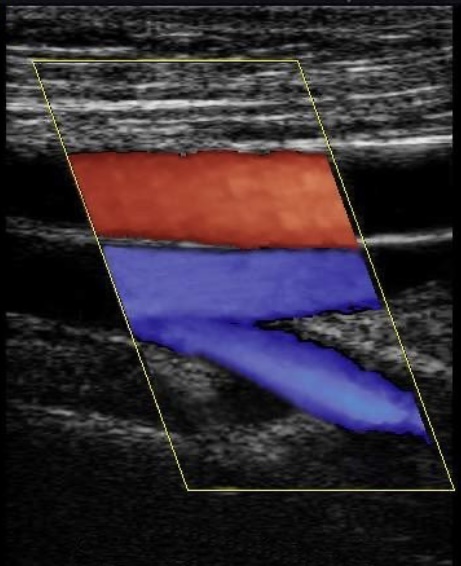

Узи сосудов в мурманске

Узи сосудов в мурманске 104 фотографий